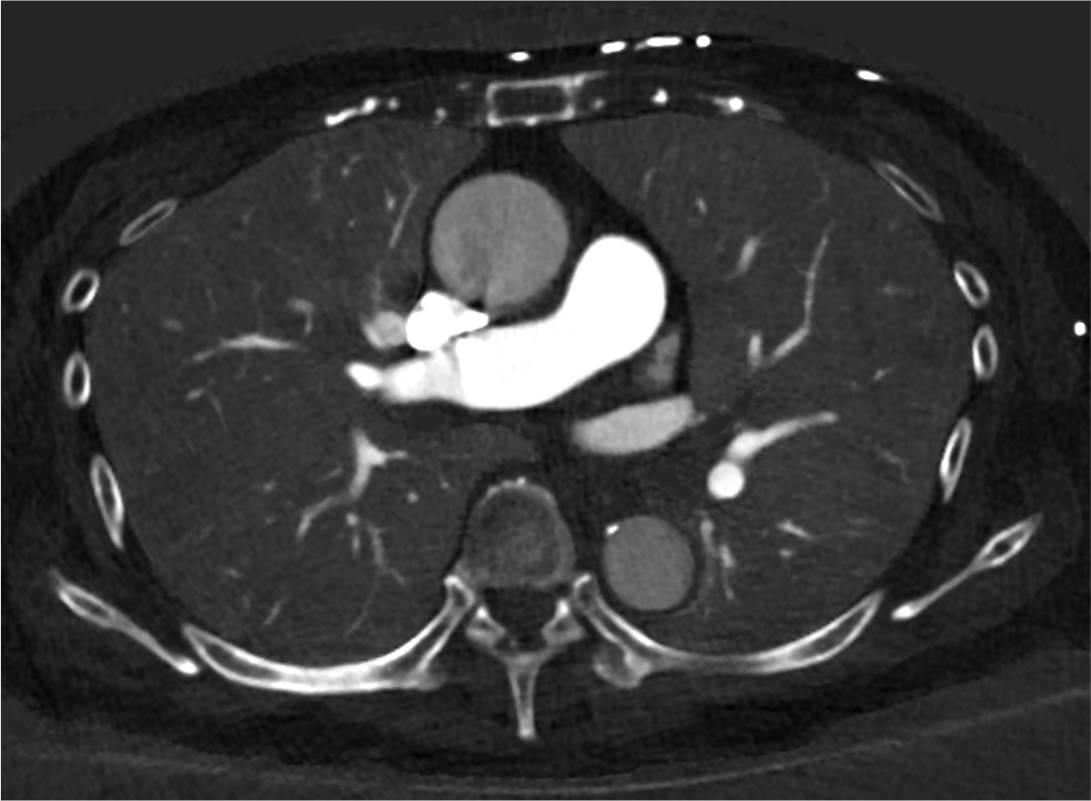

深部静脈血栓症(Deep Vein Thrombosis:DVT)と肺血栓塞栓症(Pulmonary Embolism:PE)は静脈血栓塞栓症(Venous Thromboembolism:VTE)として一つの連続した病態として捉えられる。致死的PEの剖検検討において塞栓源の70-90%以上が下肢静脈内血栓であると報告されている(1,2。肺血栓塞栓症および深部静脈血栓症の診断、治療、予防に関するガイドライン(2017年改訂版)においても、CTは静脈造影、下肢静脈超音波検査と同様にClass I に分類されている。超音波検査のように術者のテクニックに左右されず安定した情報が得られる点でCTは優位であるが、コントラストの不足は常につきまとう問題である。造影CTにおいて動脈と異なり静脈は十分なコントラストが得られにくい。特に下肢静脈ではそれが顕著で、症例によっては造影効果がほとんど得られない場合もあり、診断に苦慮することも少なくない。Photon Counting CTは検出器の素材や構造、カウンティングメカニズムによって従来CTよりもコントラストの改善、高分解能、ノイズ低減、低被ばく撮影が可能となっており、DVT検索において有利と考えられる。

当院では右上肢にルート確保し造影剤を15秒間注入し、肺動脈prep法(閾値=100 H.U.)で肺動脈相を撮影している。腋窩から鎖骨下静脈および上大静脈内の造影剤によるアーチファクトを低減する目的で造影剤注入後に生食後押しを行っている。さらに肺動脈相の撮影は足⇒頭方向とすることで肺尖部のアーチファクト低減を図っている。また、Flash spiralモードを使用することで非常に短時間での撮影が可能となっており、通常体型の患者であれば肺動脈相の撮影時間は約2秒程度である。